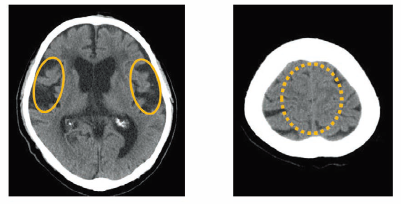

その② 正常圧水頭症

「歩くのが遅くなった」「尿の失敗が増えた」「物忘れが

気になる」。これらは単なる「年のせい」や「認知症」として

見過ごされがちですが、実は治療可能な「正常圧水頭症」

の可能性があります。

当科ではCTやMRIだけでなく、腰椎穿刺を行い、髄液を少し抜いて症状が改善するかどうかを評価します(タップテスト)。また、治療が必要と判断した場合、「L-Pシャント術(腰椎-腹腔短絡術)」を第一選択としています。

正常圧水頭症

不均等なくも膜下腔開大を有する水頭症

これは、頭蓋骨に穴を開けて脳に管を通す一般的な手術(V-Pシャント)とは異なり、脳には一切触れず、腰(脊椎)からお腹へと髄液を流す管を設置する方法です。脳への直接的な操作がないため、身体への負担が非常に少なく、高齢者でも安心して受けていただける点が大きな特徴です。歩行や生活機能を取り戻せる方を見逃さないよう、丁寧な診断と低侵襲な治療を心がけています。